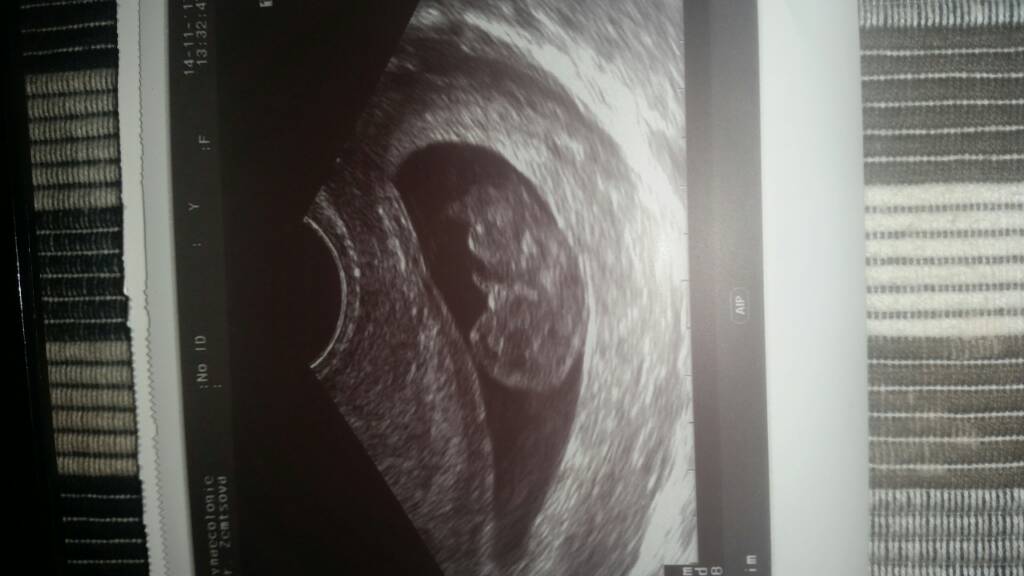

moja fasoleczka ma 24mm i słyszeliśmy serduszko [emoji7] według @ wychodzi dzisiaj 9t+3d a po usg jest 9t+1d termin porodu na 18.06 [emoji7] synek był zadowolony ze widział dzidzie. Zrobiłam od razu cała masę badań z krwi i mocz tez. Zostałam umówiona na genetyczne na 5.12 i od razu po powrocie z polski tez mnie umówiła na 8.01

dostałam jakieś różowe pudełko musze później przejrzeć co tam ciekawego jest na pierwszy rzut oka widziałam butelkę i smoczek z aventa . Dostałam 2 zdjęcia [emoji7] dzwoniłam juz do rodziców standardowo się wy płakali są prze szczęśliwi a teraz czekamy aż łaskawa teściowa u nas się zjawi żeby jej powiedzieć

Zobacz załącznik 829295